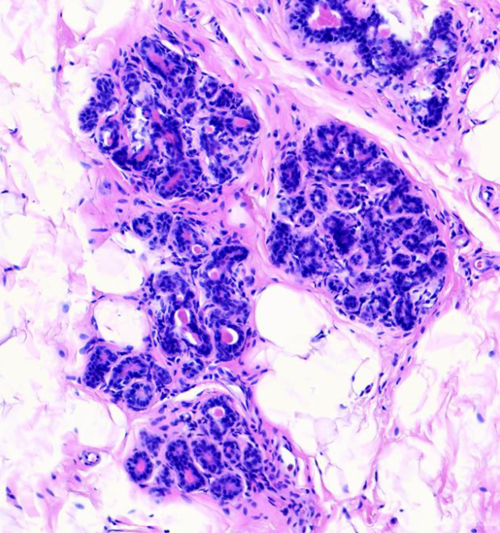

乳腺纤维腺瘤与周围正常腺体组织分界清楚,显微镜下可见其由良性的乳腺上皮和间质成分增生形成,细胞形态温和,无异型性。根据组织形态,可大致分为管内型和管周型,但分型对临床预后并无显著影响。该肿瘤经完整手术切除后,一般不会复发。

(图2:边界清晰的管内型纤维腺瘤)

(图3:管周型纤维腺瘤)